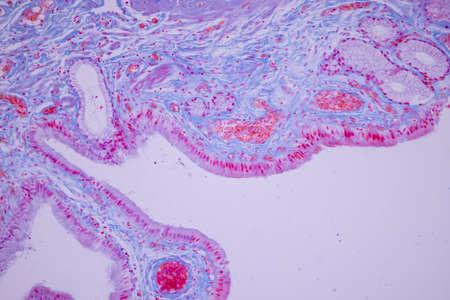

Columnar epithelium of human gall bladder under the microscope in Lab.

Columnar epithelium of human gall bladder under the microscope in Lab.

Columnar epithelium of human gall bladder under the microscope in Lab.

Columnar epithelium of human gall bladder under the microscope in Lab.